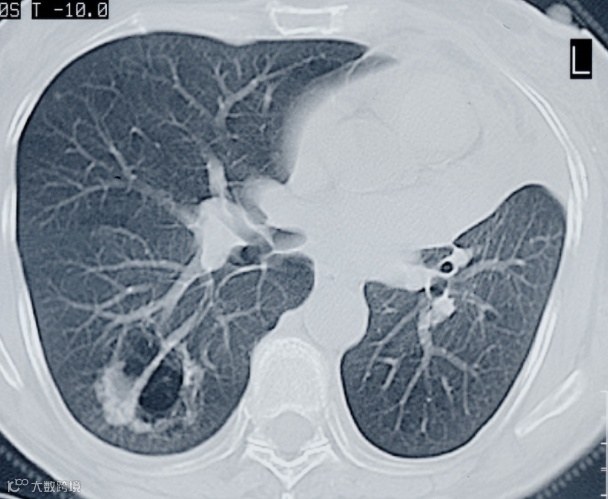

高阿姨就诊发现,她的右肺已出现大面积白色影像,几乎占据一半肺部。血液检测提示,氧合指数只有一百多,属于严重的呼吸衰竭状况。